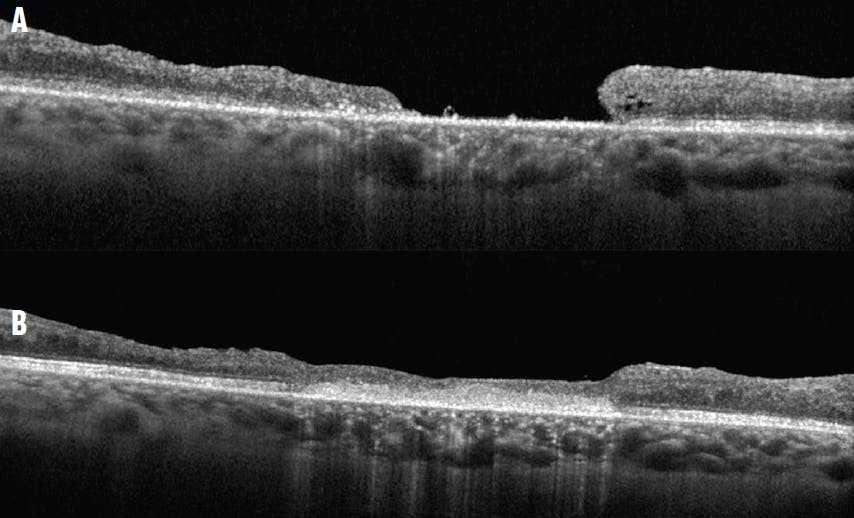

Case No. 1: A woman in her 30s with type 1 diabetes and severe nonproliferative diabetic retinopathy who developed vitreomacular traction and an epiretinal membrane (ERM) underwent PPV with ERM and ILM peeling and gas tamponade. After surgery, she developed a large full-thickness MH for which she underwent a second PPV with additional ILM peeling and gas tamponade. The MH failed to close, and she was referred to us for a second opinion (Figure 1A). At initial presentation to our clinic, her VA was counting fingers. We performed MH hydrodissection, MH massage, subretinal AM placement, and SF6 gas. Her VA improved to 20/100 approximately 9 months postoperatively (Figure 1B).

Figure 1. Preoperative OCT imaging shows a large MH measuring approximately 1,300 µm with a flat-open configuration (A). OCT imaging obtained 9 months after PPV, MH hydrodissection, MH massage, subretinal AM placement, and SF6 gas shows closure of the hole (B).

Preoperative OCT imaging for the patient in the first case showed a large irregular MH measuring approximately 1,300 µm at the narrowest inner diameter. Importantly, the hole had a flat-open configuration, as opposed to the anvil configuration typically seen with acute idiopathic MHs in which the MH edges (often with cystic changes) are slightly elevated by a cuff of subretinal fluid. Th flat-open configuration may indicate the presence of retina–RPE adhesions and may alert the surgeon that, for the edges to mobilize, hydrodissection or blunt dissection may be helpful. The same may be necessary for an AM to be easily positioned subretinally and anchored under the MH’s edges. In the first case, lysis of the adhesions was required before an AM could be introduced into the subretinal space.